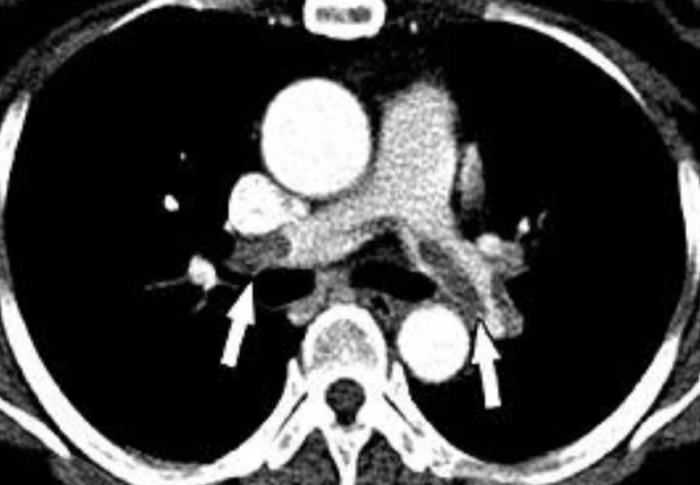

Kết quả CT cho thấy bệnh nhân thuyên tắc động mạch phổi 2 bên (Ảnh: BS)

Theo báo cáo, bệnh nhân ban đầu hồi phục bình thường nhưng chỉ sau khoảng 48 giờ xuất hiện khó thở, tụt huyết áp, giảm oxy máu. Ban đầu, ê-kíp nghi ngờ phản vệ độ 3, tuy nhiên kết quả thăm khám và cận lâm sàng cho thấy người phụ nữ bị thuyên tắc mỡ và thuyên tắc phổi do mỡ - một biến chứng cực kỳ nguy hiểm của hút mỡ.